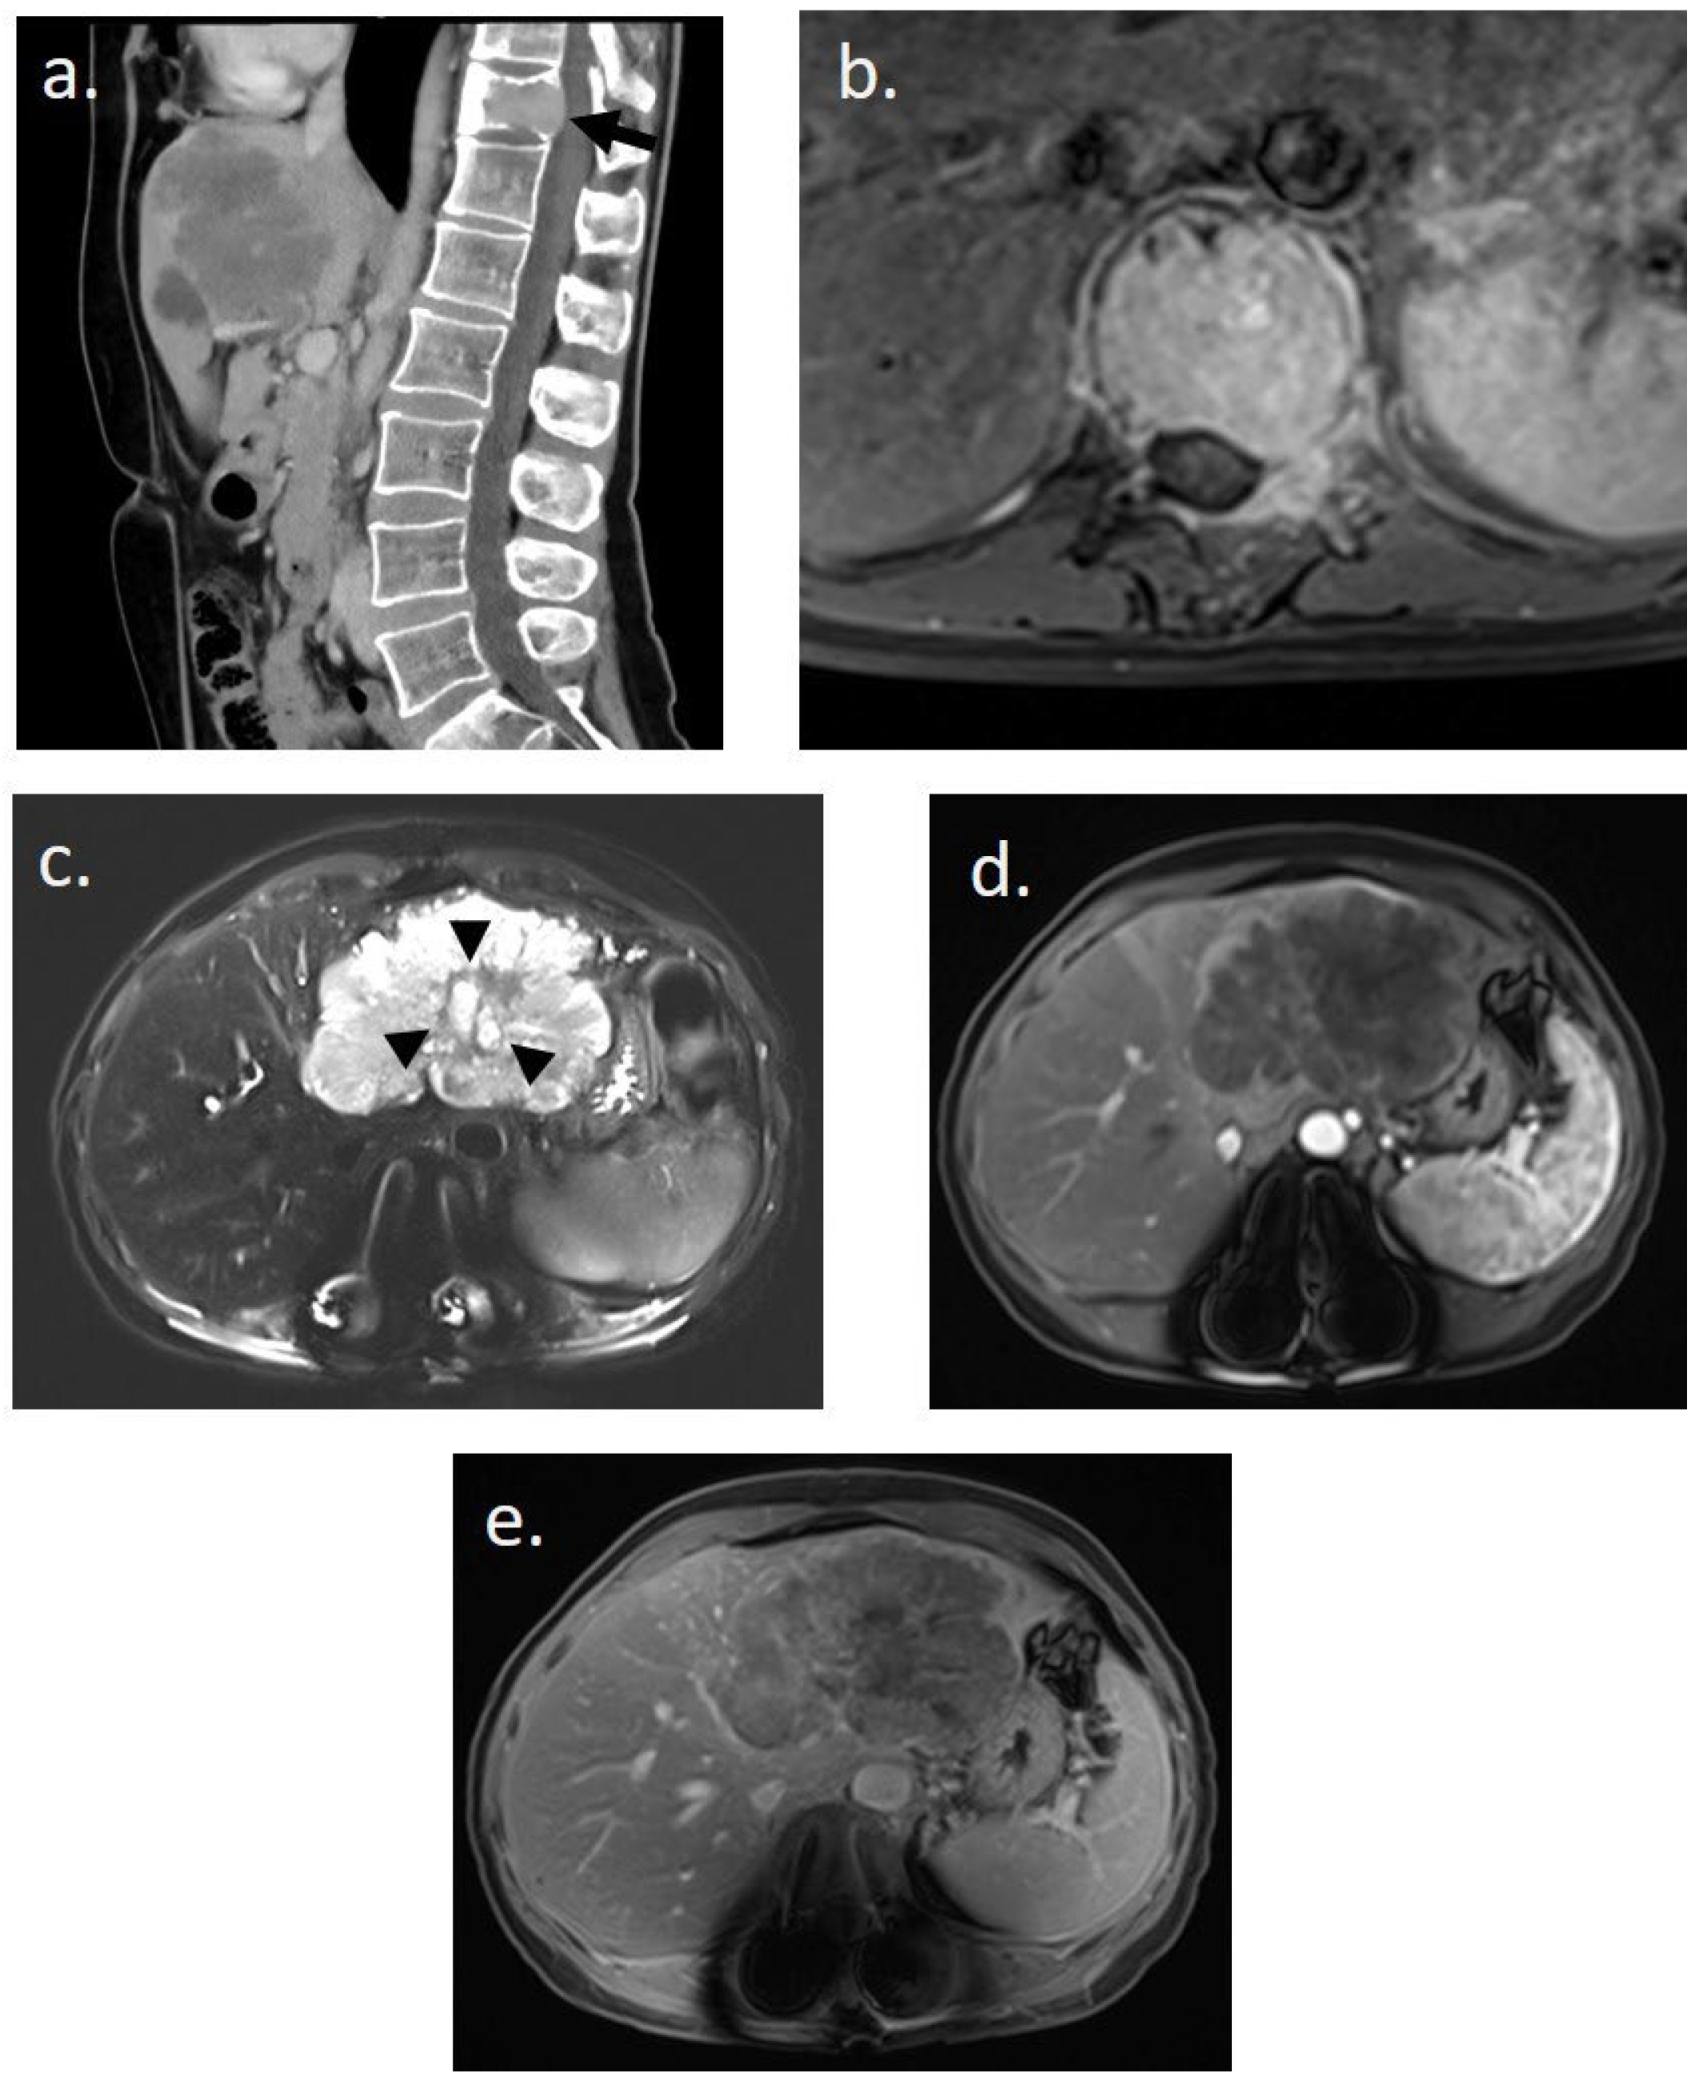

2. Case Presentation